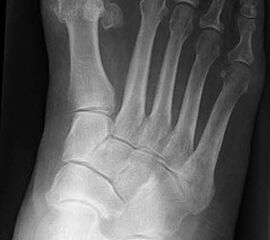

Stehende konventionelle Röntgenbilder eines Fußes mit Planovalgus Deformität Stadium II b dorsoplantar (dp) und seitlich. Auf der dp-Aufnahme zeigt sich die talo-calcaneare Divergenz, der gegenüber dem Kalkaneus nach anterior gleitende Talus und d

Stehende Aufnahmen des Fußes dorsoplantar (dp) und seitlich sowie des OSG anteroposterior (ap) sind die Grundlage der konventionellen Röntgendiagnostik (Abb. 5). Ergänzend werden gelegentlich die Rückfuβ-Alignement Aufnahme nach Saltzman 19 und Vergleichsaufnahmen der Gegenseite durchgeführt.

Der Talo-Metatarsale I Winkel bzw. die laterale talonaviculare Subluxation auf der stehenden dorsoplantaren Aufnahme des Fuβes dokumentieren das Ausmaβ des Vorfuβ abductus (Abb. 6 a,b). Ein dp Talo-Metatarsale I Winkel von > 10° (nach medial konvex) ist als pathologisch anzusehen. Mit der Bestimmung der talocalcanearen Divergenz (Abb. 6 c) erhält man ein Eindruck über das Ausmaβ des Rückfuβ valgus; eine leichte Divergenz bis ca. 12° gilt als physiologisch 20.

Auf der seitlichen, stehenden Aufnahme des Fußes wird ebenfalls der laterale Talo-Metatarsale I Winkel (Abb. 6 d) gemessen und so das kollabierte mediale Längsgewölbe dokumentiert. Auch hier gilt ein Talo-Metatarsale I Winkel von > 5° (nach plantar konvex) als pathologisch 21. Der Kollaps findet dabei meist im Talonaviculargelenk, seltener in der Naviculocuneiform-Gelenkreihe statt. Instabilität und Arthrose im 1. TMT sollten ausgeschlossen oder bei der Operationsplanung mit einbezogen werden. Weitere wichtige radiologische Messungen zur Beurteilung der Planovalgus-Statik und Progression der Deformität sind der laterale talo-calcaneare Winkel (Abb. 6 e) und der Abstand des Os cuneiforme-Unterrandes zum Untergrund (Abb. 6 f, Cuneiform height, 22. Eine anteriore Translation des Talus auf dem Kalkaneus findet man sowohl auf der ap, als auch auf der seitlichen Aufnahme des Fuβes mit Aufhebung der Cima-Linie.